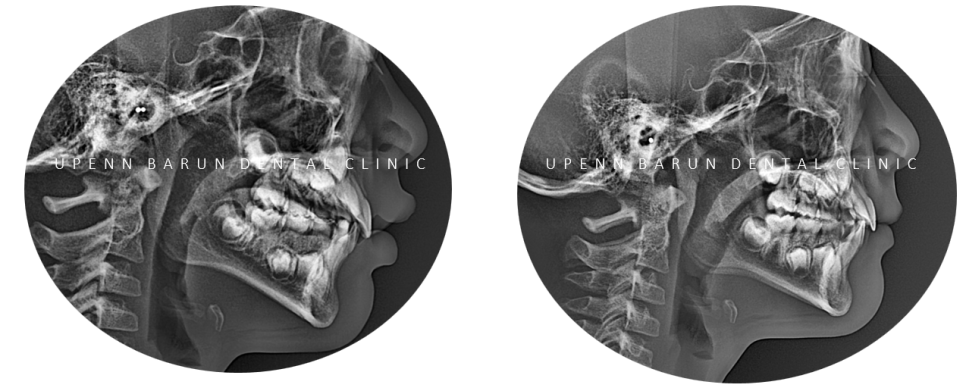

먼저 닥터킴의 정밀한 진단을 위해

i-TERO 로 구강내 스캔을 해보았습니다.

유펜바른치과의

정밀진단 결과

치아가 너무 깊게 물리는 과개교합

상태였습니다.

과개교합은

윗니가 아랫니를 비정상적으로 깊게 덮고 있어

아랫니가 잘 보이지 않고

어린 나이에도 불구하고

아래 치아에 마모가 관찰되는 것이 특징입니다.